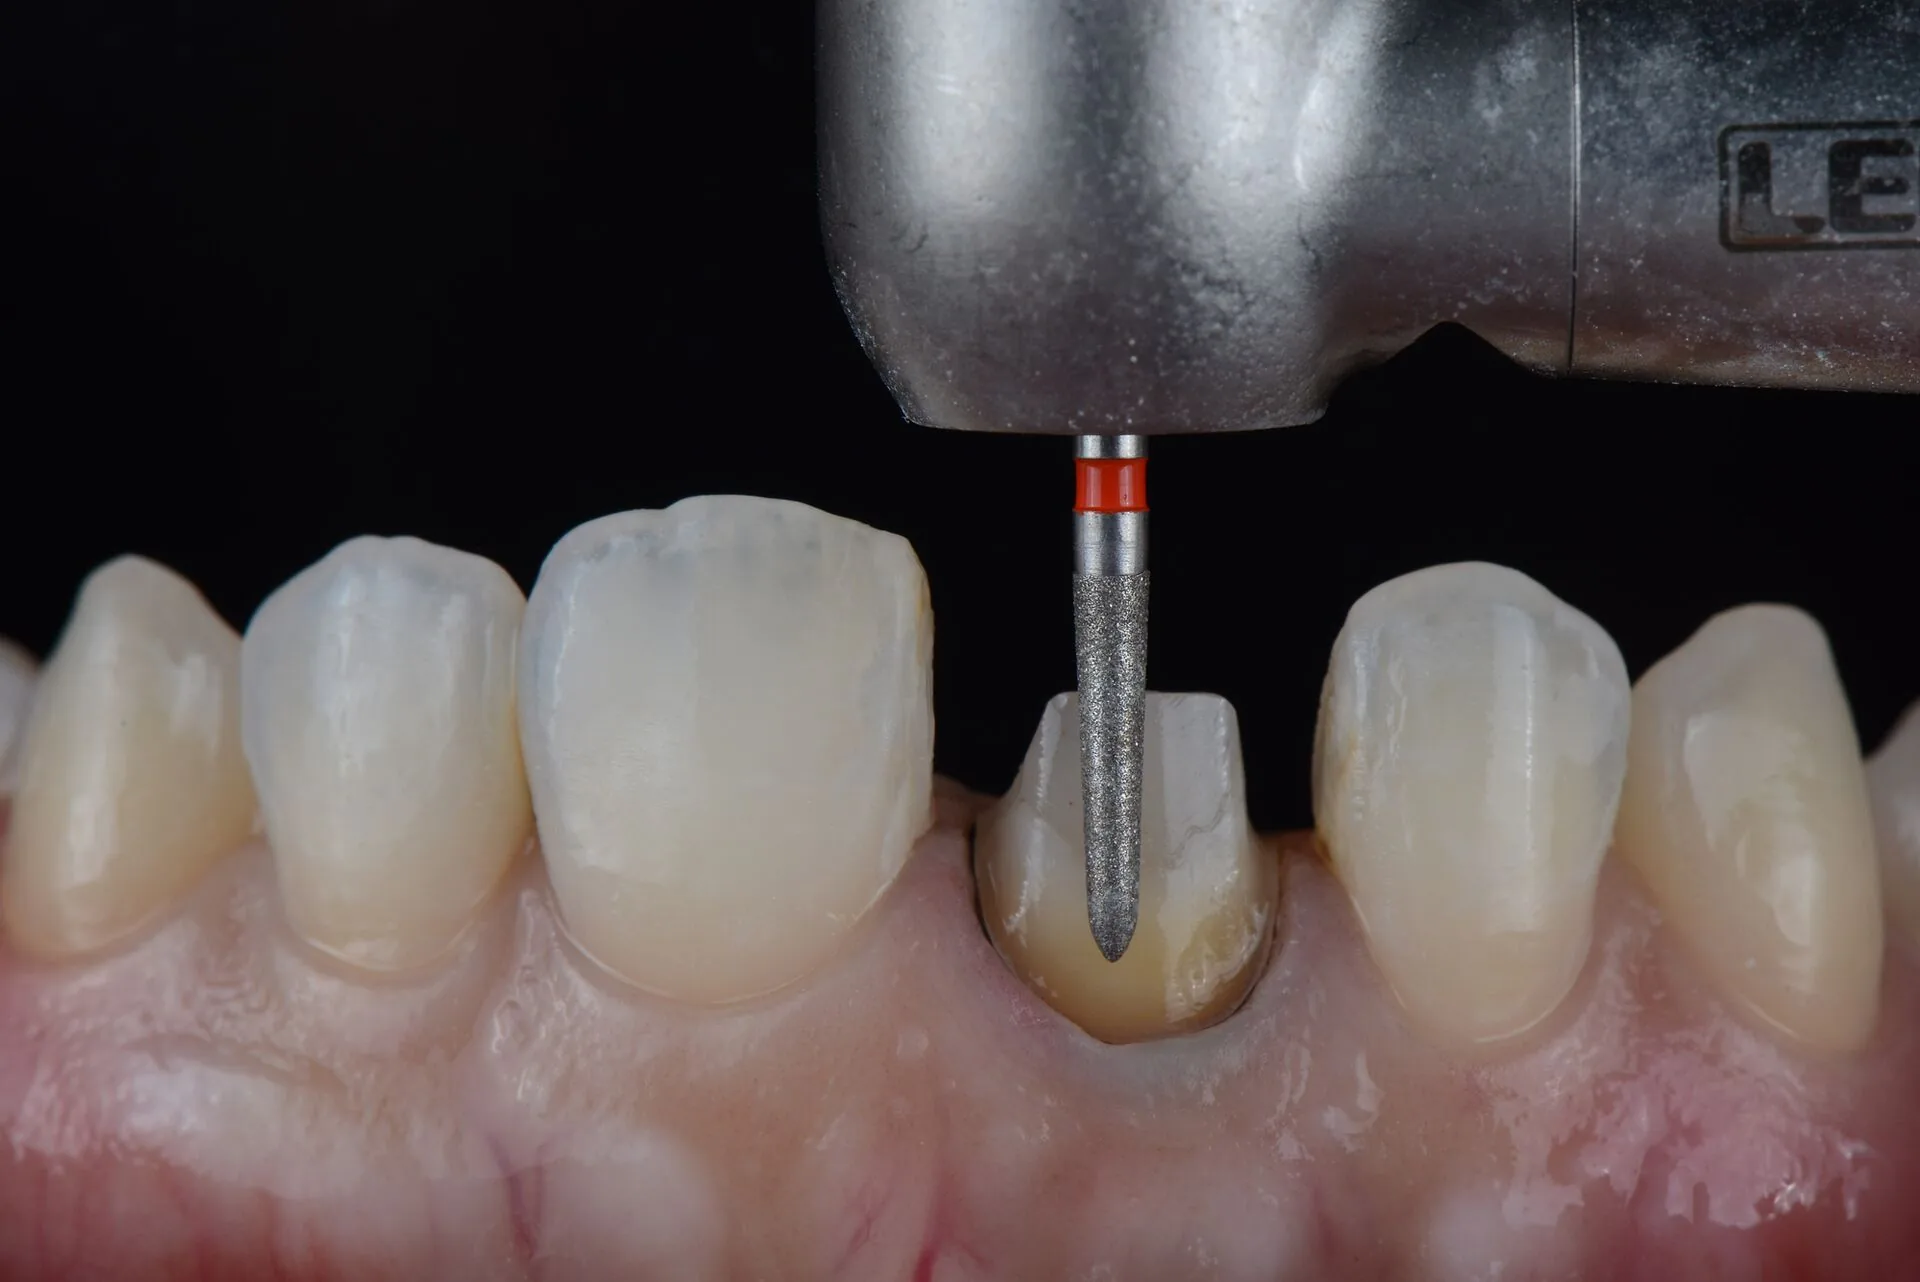

Что за процедуры были сделаны?

Аноним 15/08/25 Птн 19:42:15 1636217 45

>>1636160

Это разные люди, носы разные. Справа настоящие, просвечивающие зубы. Т.е. справа могло быть только до, а слева после. А вот причина - бруксизм или получение в табло - это вопрос открытый. Ну либо такие виниры люминиры научились делать лайк рил тиз.